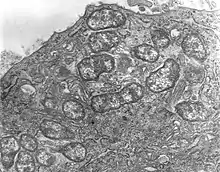

| Orientia tsutsugamushi | |

Scrub typhus or bush typhus is a form of typhus caused by the intracellular parasite Orientia tsutsugamushi, a Gram-negative α-proteobacterium of family Rickettsiaceae first isolated and identified in 1930 in Japan.[2][3]

Although the disease is similar in presentation to other forms of typhus, its pathogen is no longer included in genus Rickettsia with the typhus bacteria proper, but in Orientia. The disease is thus frequently classified separately from the other typhi.